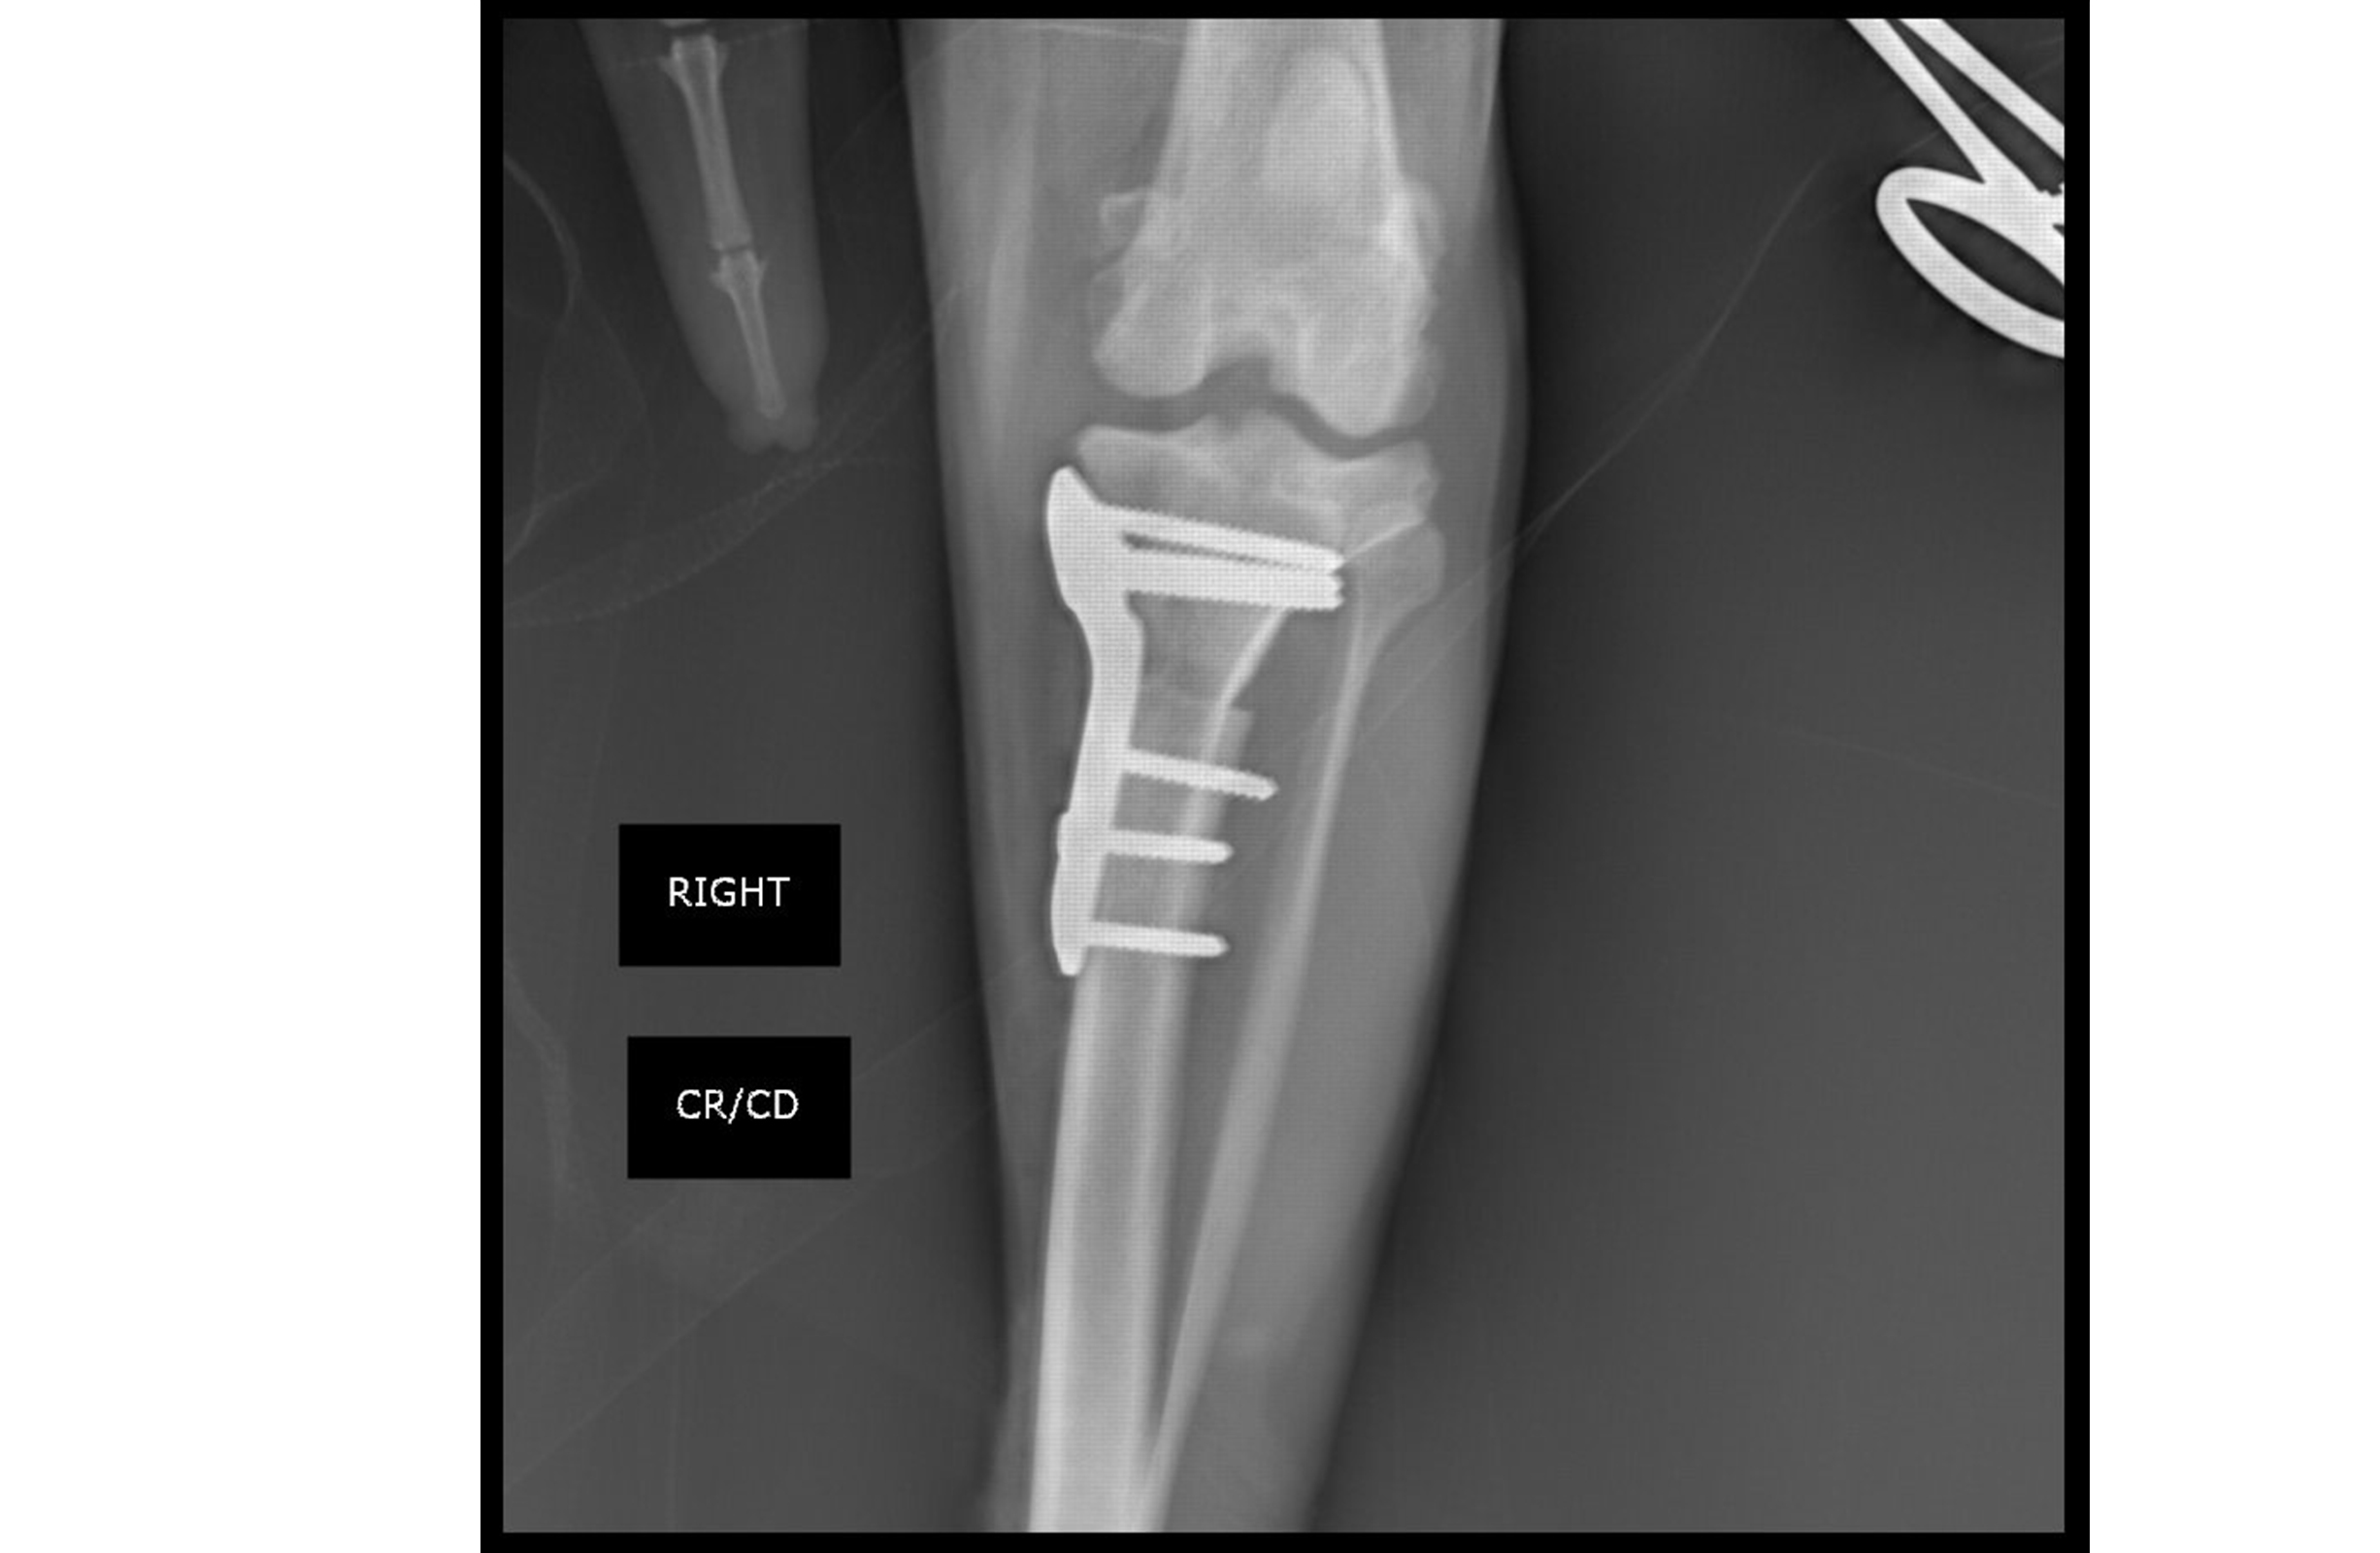

To help Kona regain comfortable movement, Dr. Keoughan performed a tibial plateau leveling osteotomy (TPLO) using the Arthrex TPLO Locking Plate System.

After adjusting the bone angle, he secured the knee using a locking plate and screws designed specifically to fit a dog’s anatomy.

For surgeries like TPLO, using high‑strength stainless steel or titanium alloy plates that fit the natural curve of a pet’s bone can help reduce complications and support a smoother recovery.